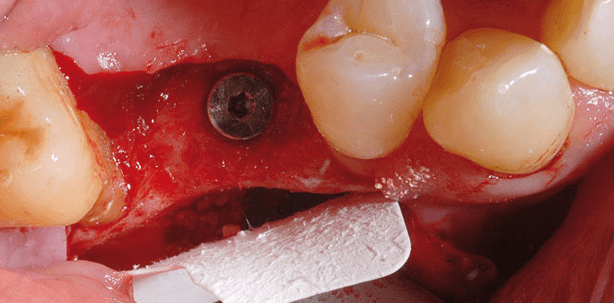

Auch in diesem Fall wünschte die Patientin eine festsitzende Prothetik für ihre Lücke im rechten Oberkiefer (Abb. 8 und 9). Geplant war wieder ein Sinuslift mit Augmentation und Implantation von drei Nobel Active-Implantaten in einer Sitzung. Die operative Vorgehensweise ist entsprechend Fall 1. Allerdings musste das mittlere Implantat mit einem heterologen Knochenblock (purosallograft Block, Zimmer dental, Freiburg im Breisgau) fixiert werden, um bei der ausgesprochen reduzierten vertikalen Knochenresthöhe von 2 mm mit dem Nobel-Active-Implantat die Primärstabilität zu erreichen. In den spongiösen Block wurde ein Loch vorgebohrt, leicht untermassig zum Implantat Regio 15 (Durchmesser 3,5 mm, Länge 13 mm) (Abb. 10). Bei dem vorsichtigen Inserieren des Implantats wirkt die Geometrie des Nobel Active-Implantats wie eine Stabilisierungsschraube, die den Knochenblock von innen anzieht. Aufgrund dieses speziellen Implantattyps konnte eine zusätzliche Fixierung des Knochenblocks entfallen. Positiv war auch in diesem Fall, dass es beim Eindrehen des Implantats nicht zum Ausbrechen fragiler lateraler Knochenanteile kam. Der Defekt wurde mit einer Mischung aus Eigenknochen und Bio-Oss (Geistlich, Baden-Baden) aufgefüllt. Insgesamt wurden drei Implantate (alle Länge 13 mm, Durchmesser 3,5 mm) inseriert. Die Membran wurde zur Abdeckung des Defekts (Abb. 11) leicht aufgelegt. Auf eine Pinfixierung konnte verzichtet werden. Die Röntgenkontrolle (Abb. 12) nach dem Eingriff zeigt die Stabilisierung der knöchernen Verhältnisse. Die prothetische Versorgung der Patientin erfolgt exakt sechs Monate nach der OP. Auch sie erhält drei Kronen, die miteinander verblockt werden.